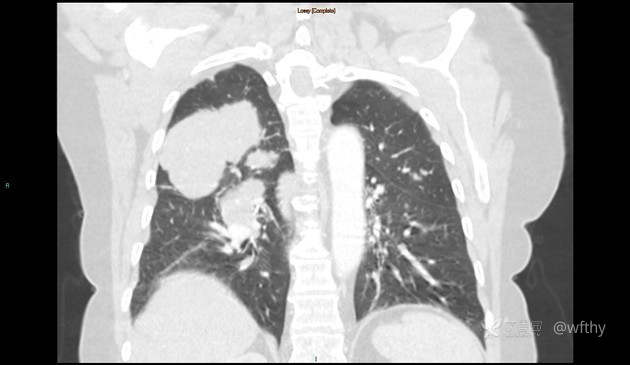

病例女65,头部肿块